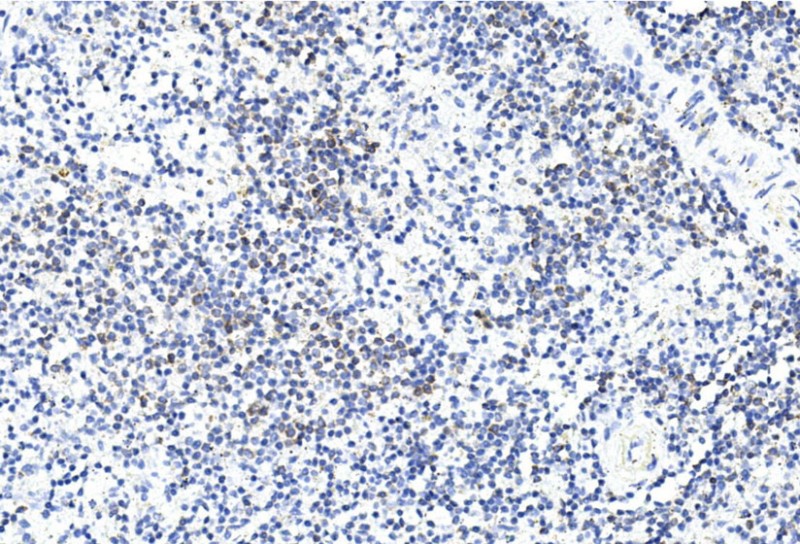

- Immunohistochemical analysis of paraffin-embedded mouse spleen section using GREMLIN Antibody (C-term) (Cat#P34598). P34598 was diluted at 1:200 dilution. A undiluted biotinylated goat polyvalent antibody was used as the secondary, followed by DAB staining.

- Immunohistochemical analysis of paraffin-embedded human spleen section using GREMLIN Antibody (C-term) (Cat#P34598). P34598 was diluted at 1:200 dilution. A undiluted biotinylated goat polyvalent antibody was used as the secondary, followed by DAB staining.